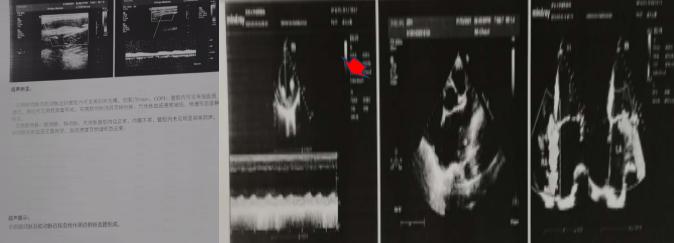

2021年1月20日心血管內(nèi)科二病區(qū)接診一位56歲男性患者,以“右上肢疲乏無力“之主訴入院,患者右側(cè)橈動脈搏動消失、血壓無法測出。此患者發(fā)生了什么?患者基礎(chǔ)病為1.冠心病 急性非ST段抬高型心肌梗死 心房顫動2.腦梗死,為什么右橈動脈搏動消失、血壓無法測出?迅速聯(lián)系超聲室王英莉副主任和賈貝醫(yī)生,迅速對患者右上肢動脈、心臟超聲進(jìn)行檢查,結(jié)果示:左心房內(nèi)附壁血栓,其表面血栓動度明顯,存在再次脫落風(fēng)險,上肢動脈后提示閉塞伴側(cè)枝血管形成。心血管內(nèi)科二病區(qū)主任左梅教授再次對患者進(jìn)行診查,建議立即啟動溶栓治療。經(jīng)過連續(xù)5天的治療,患者的右橈動脈可觸及,血壓126/74mmHg。那么患者為什么會發(fā)生栓塞?栓子從哪里來?